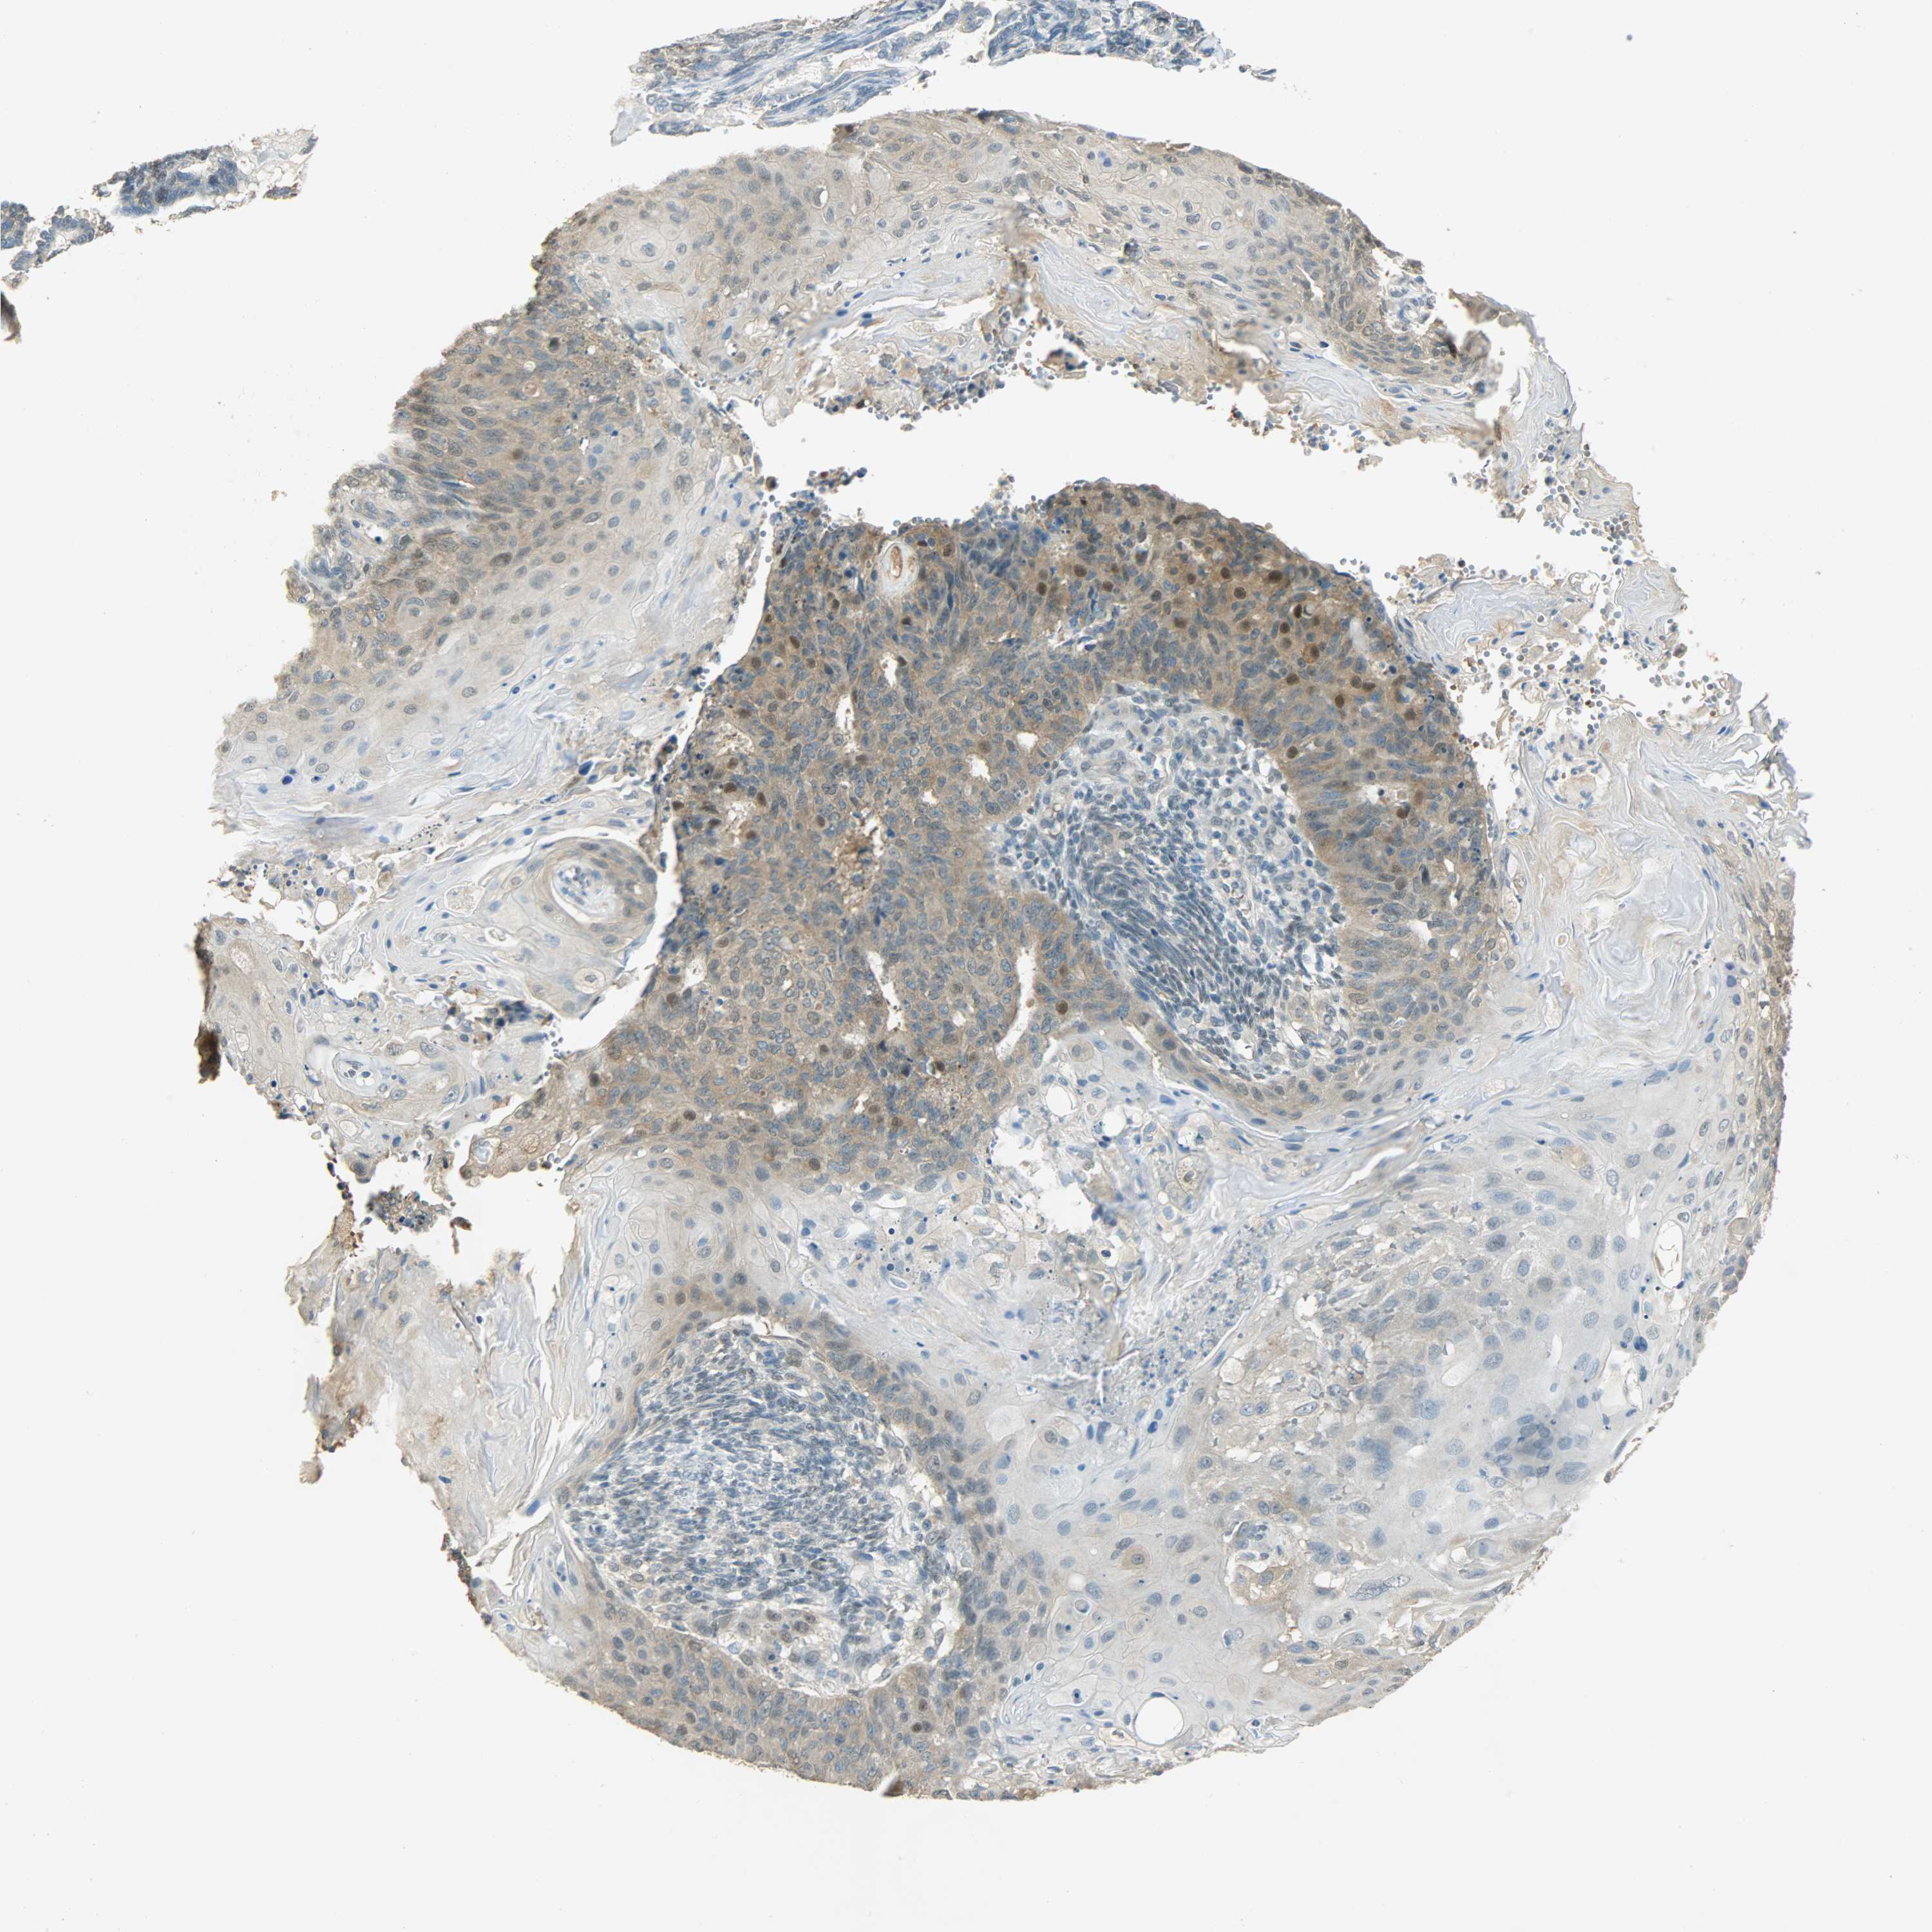

ENDOMETRIAL CANCER - Protein expressioni

A mouse-over function shows sample information and annotation data. Click on an image to view it in a full screen mode. Samples can be filtered based on level of antibody staining by selecting one or several of the following categories: high, medium, low and not detected. The assay and annotation is described here.

Note that samples used for immunohistochemistry by the Human Protein Atlas do not correspond to samples in the TCGA dataset.

Antibody stainingi

Antibody staining in the annotated cell types in the current human tissue is reported as not detected, low, medium, or high, based on conventional immunohistochemistry profiling in selected tissues. This score is based on the combination of the staining intensity and fraction of stained cells.

Each image is clickable and will lead to virtual microscopy that enables deeper exploration of all samples and also displays staining intensity scores, fraction scores and subcellular localization as well as patient and tissue information for each sample.

Antibody HPA005525

Antibody HPA064708

Antibody CAB012459

Staining

High

Medium

Low

Not detected

Intensity

Strong

Moderate

Weak

Negative

Quantity

>75%

75%-25%

<25%

None

Location

Nuclear

Cytoplasmic/membranous

Cytoplasmic/membranous,nuclear